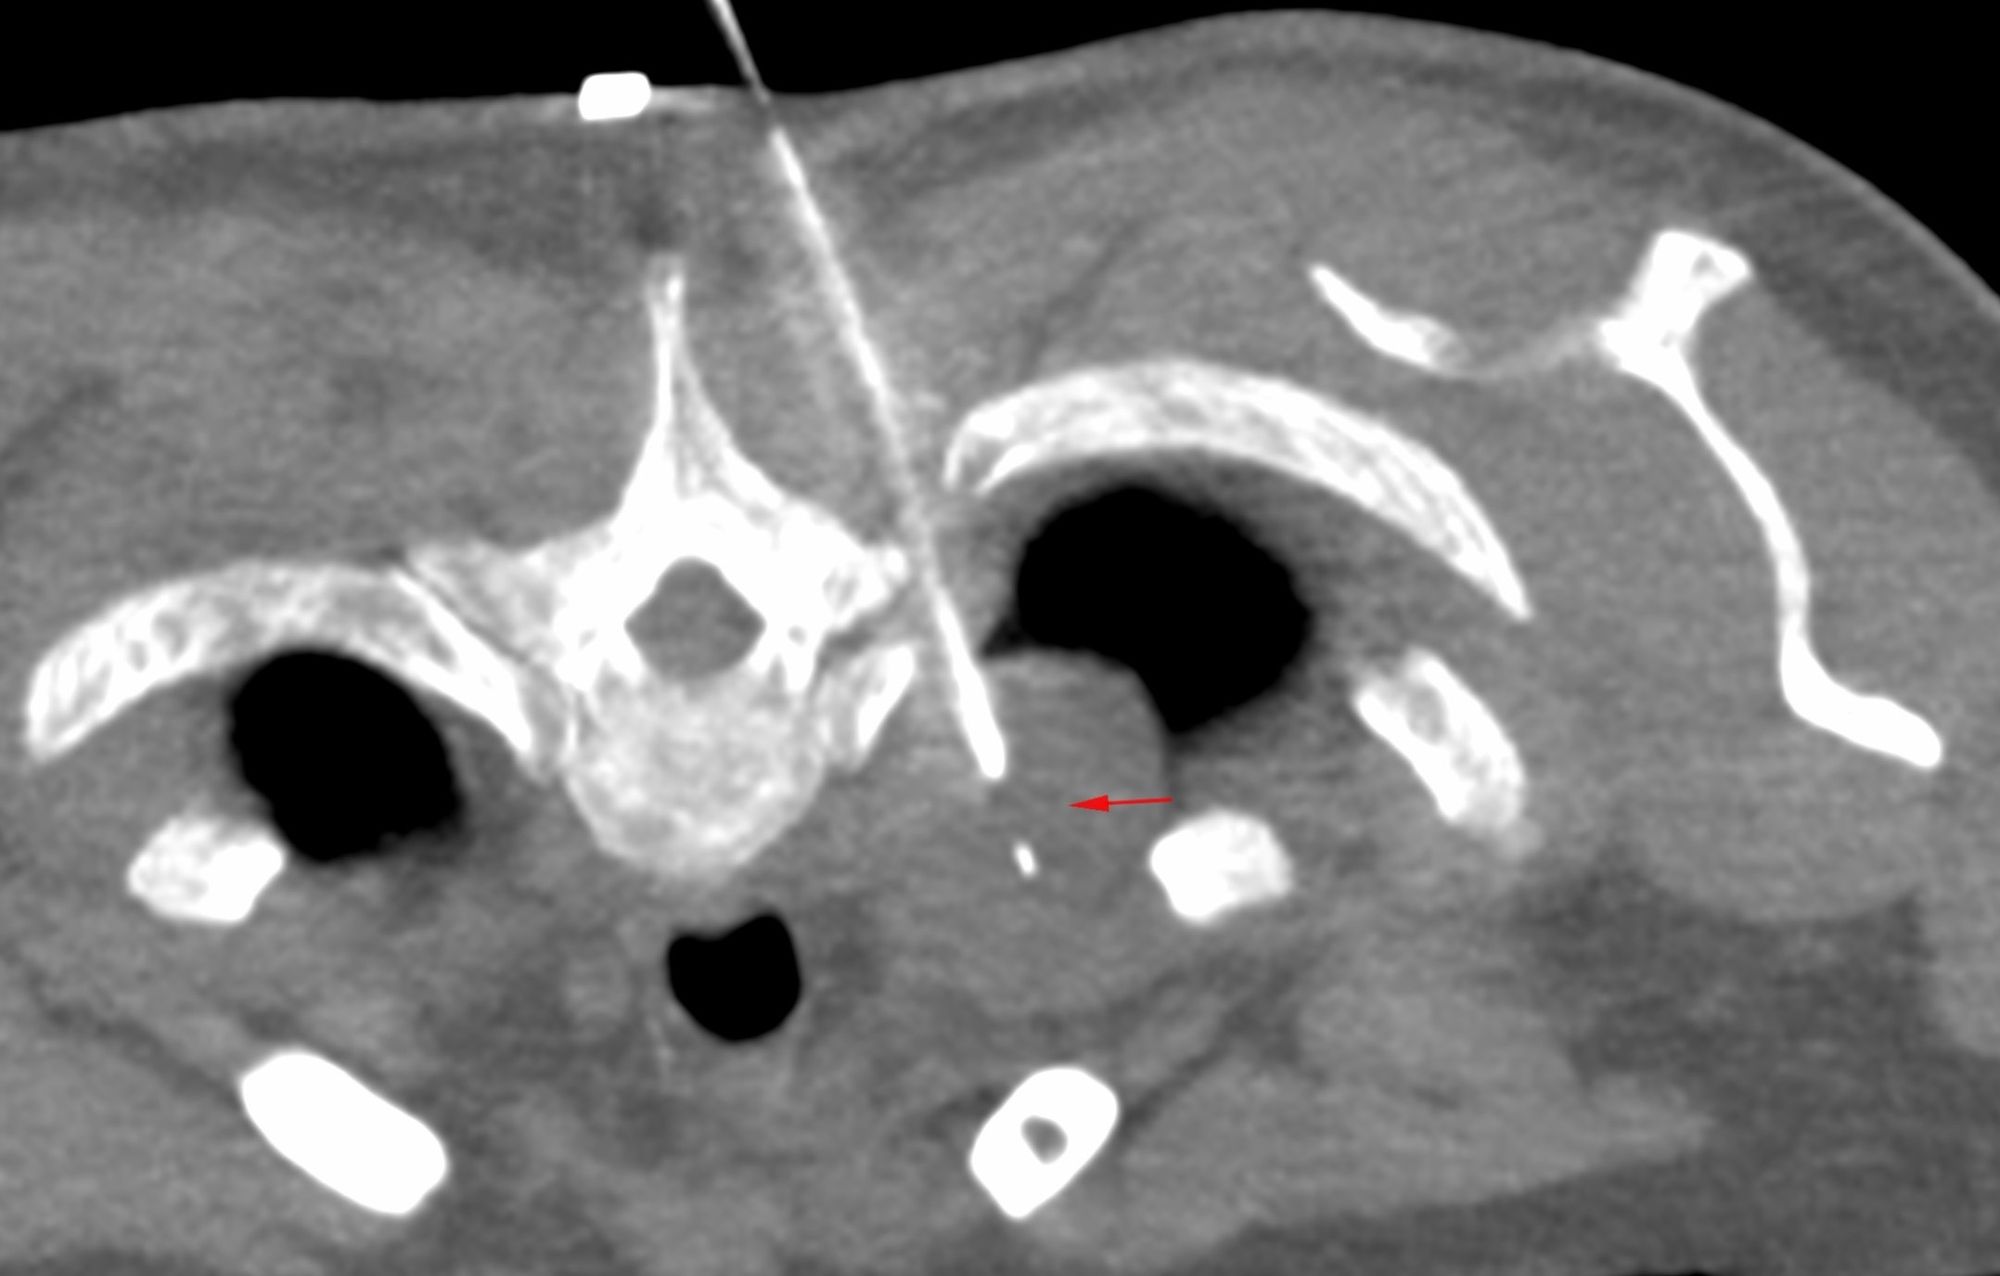

Case 38: Transsternal Biopsy of a Pretracheal Space Mediastinal Mass